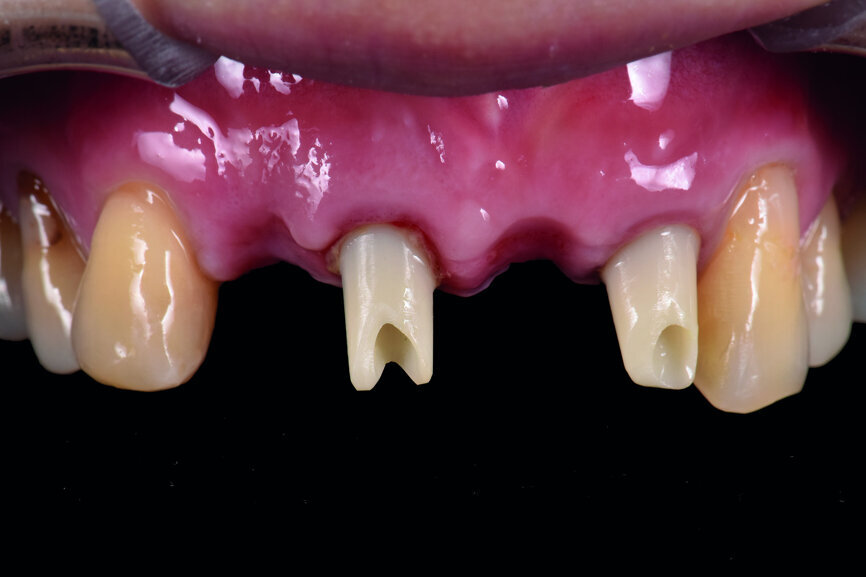

A 40-year-old female patient had sustained trauma to her anterior teeth caused by accidental syncope three weeks before. The clinical examination found that tooth #11 had been luxated; the crowns of teeth #12 and 21 had fractured, with the residual margin extending 3–5 mm below the gingiva and the teeth affected by Grade III mobility; and the crown of tooth #22 had fractured, with the residual margin at gingival level. There were no obvious abnormalities in the remaining teeth (Figs. 1–4). After excluding major systemic diseases, it was decided that she required fixed implant restoration with high demands regarding aesthetics and function.

Fig. 2: Pre-op occlusal view of the anterior teeth.